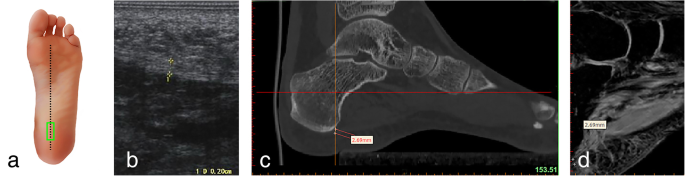

Ultrasound, CT, and MRI measurements of the thickness of the plantar fascia at its origin (longitudinal section) a Ultrasonic probe is placed (green panel). b Ultrasonic measurement. c Measuring the thickness of the plantar fascia econstruction CT images. d Measuring the thickness of the plantar fascia reconstruction MRI images

Measurements of the plantar fascia thickness were taken using HIVISION Preirus ultrasound systems (Hitachi Ltd., Japan) with a linear 5 to 13 MHz transducer. The patient was asked to lie in a prone position with the bilateral lower limbs in full extension and both ankles at 90°. The probe of the ultrasound was placed on a line connecting the second toe and the midheel. The thickness of the plantar fascia was determined at its proximal end, close to the insertion point into the calcaneus, by longitudinal sonograms of the heel [15] (Figs.1a, b and 2a, b); then, readings were also taken at the arch of the foot in the central metatarsal zone (Figs. 3a, b, and 4a, b). Finally, the thickness of the plantar fascia was measured between the base of the first and second toes (Fig. 5a, b and 6a, b). Additionally, the echo changes were observed in two sections, and the thickness and echo of the plantar fascia were observed and measured in the longitudinal section and in the cross-section, respectively. The ultrasound examinations were performed by two physicians, both of whom had rich experience in the diagnosis of musculoskeletal conditions, and the reliability of the repeated measurements between the evaluators was evaluated.